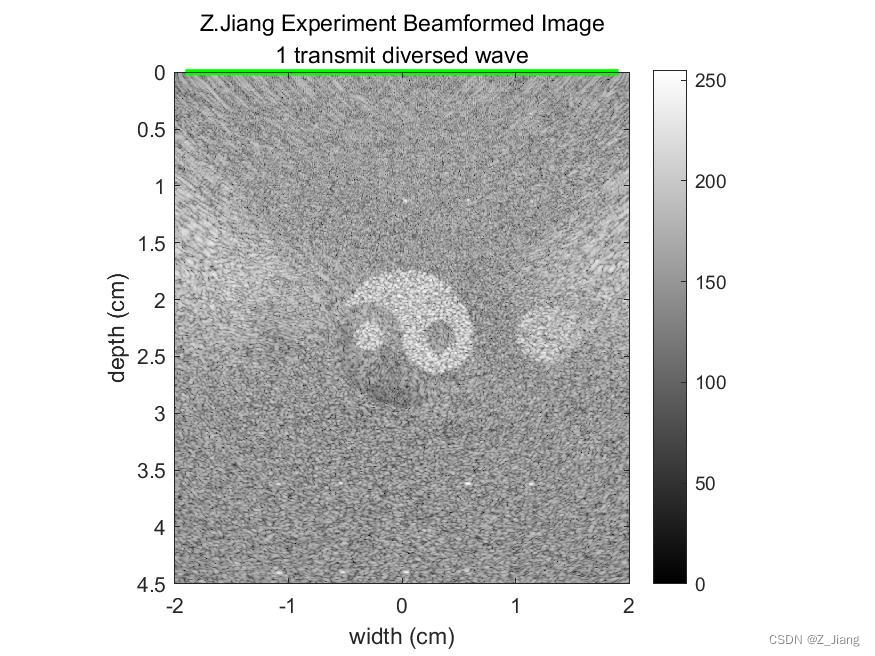

下面我做个极端例子,使用128晶元线阵探头,平面波发射,只做一次发射打开全部晶元,波束合成时,接收MLA=512,覆盖整个成像区域,情况如下

相同的情况,换作发散波,单次发射,打开全部晶元,MLA=512,覆盖全区域,结果如下

左:体模 中:单次全孔径平面波 右:单次全孔径发散波

扩散波与平面单次发射,全区域成像结果比较类似。我们可以发现,这两种发射由于成像区域内没有焦点,也就不存在无声区,即使我做到512的MLA覆盖4厘米的宽度,也不会出现暗黑的无声区域。另外,大家应该留意到MLA的BLOCK格子也不会存在。因为声压全场统一,不会由于不同的MLA线处声压强度,导致MLA线实际位置横向偏移,同时这种极端扫查情况下,帧速率(FPS)可以做到每秒几千甚至上万。可以把这样的优势用在需要高帧速的场景,更精细的运动追踪,时间解析度更高的造影等等。

但缺点也很明显,grating lobe伪影明显,信噪比低,分辨率差等。在实际系统设计上,我们肯定使用更小的孔径,更少的MLA,多次发射,降低FPS,来平衡图像品质。